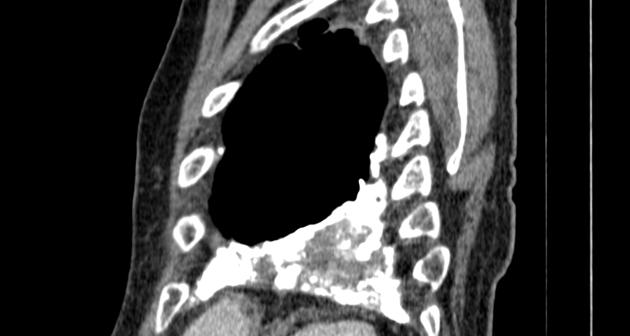

Même cas en coupe

sagitale . Aspect radiologique de epaissisement

pleural diffuse est de plaque opacite hyperdense ,

heterogene situe à inferieure , posterieure au sinus

coste-diaphragmatique posterieure droite . Image

radiologique TDM en coupe sagitale fenetre

mediastinale . |